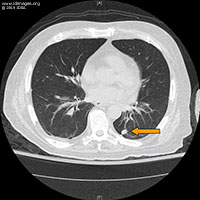

- The patient was admitted to the hospital and was scheduled for a Magnetic Resonance Imaging (MRI) of the brain. On day 2 his neurological status rapidly deteriorated. He became acutely confused and obtunded requiring intubation for airway protection and transfer to the medical intensive care unit. His temperature increased to 100.4°F (38.0°C) and he was empirically started on vancomycin, meropenem and acyclovir. Infectious diseases service was consulted. Brain MRI showed diffusion restriction and corresponding high T2 and FLAIR signal involving the tectum and midline periaqueductal region of the midbrain and a small area of the medial superior left cerebral hemisphere; there was midbrain edema with associated stenosis of the aqueduct and obstructive hydrocephalus of the third and lateral ventricles (Figure 3A and B).

- Figure 3: MRI brain without contrast on day 3. (A) Sagittal FLAIR images showing area of hyperintensity in the tectum and midline pre-aqueductal region of the midbrain. Associated stenosis of the aqueduct with obstructive hydrocephalus. (B) Diffusion-weighted imaging showing high-signal areas in a small area of the medial superior left cerebral hemisphere. There was no definite corresponding apparent diffusion coefficient changes.